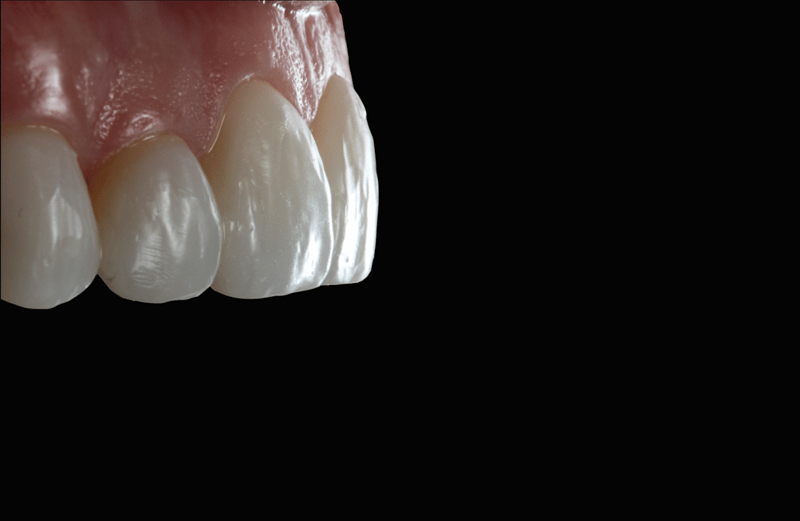

- Komposit-Applikation: Applikation von Transcend Komposit (Farbe B1D ), beginnend mit einem 2/3 Abstand von der Inzisalkante. Allmähliche Ausdünnung in Richtung Gingiva. Applikation der Farbe „Universal Body“ (UB) nahe des gingivalen Drittels. Auftragen der finalen Schichten mit Enamel White (EW) und einer kleinen Menge UB am gingivalen Rand, um einen natürlichen Farbverlauf zu erzielen.

- Konturierung der Ränder: Konturierung der Ränder mit einem feinen Mosquito-Diamantbohrer zur gewünschten Form.

- Faziale Anatomie: Verwendung von kugelförmigen und langen, dünnen Diamantbohrern zur Ausgestaltung der fazialen Anatomie. Erstpolitur mit Jiffy™ Natural Polierern. Hochglanz-Finish zum Erhalt der tertiären Anatomie mit Ultradent™ Diamond Polish Mint und Jiffy™ Goat Hair Brush (in Europa nicht verfügbar).